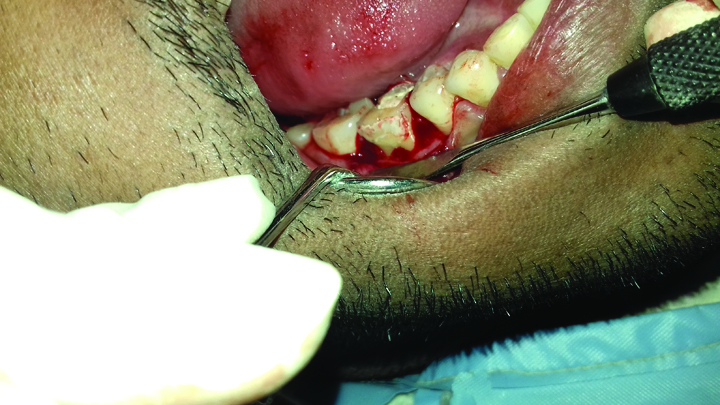

After two weeks, the post obturation restoration was done with composite resin (TPH, Dentsply) and then a surgical procedure was carried out for intentional bicuspidisation of the tooth. After removal of the orthodontic band, a full thickness Kirkland flap was raised with the cervicular incision extending from the distal surface of the mandibular second premolar to the midfacial surface of the mandibular second molar [Table/Fig-6]. After flap elevation, the tooth was dissected with the help of a long shank tapered fissure carbide bur to make vertical cuts towards the bifurcation area. All faces of the mesial and distal roots were rounded up and the spurs were smoothened. After irrigation with saline solution, the flap was repositioned and sutured with 3/0 silk sutures [Table/Fig-7].

Kirkland flap raised in relation to 46.